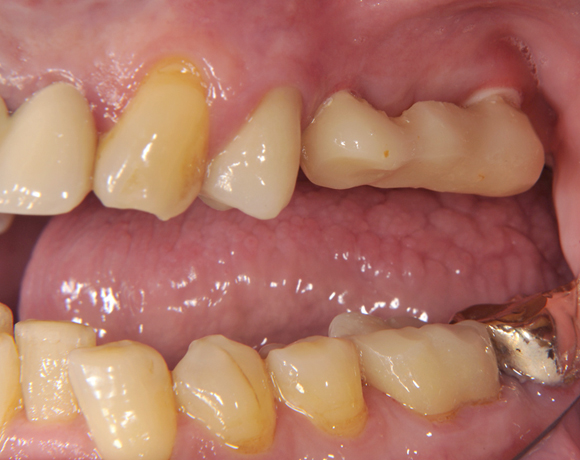

Im vorliegenden Patientenfall wurden für die Zähne 25 und 27 jeweils ein Implantat gesetzt. Nachdem die Implantate eingeheilt waren, wurde 25 – 27 mit einer Brücke versorgt.

Der prothetische Teil